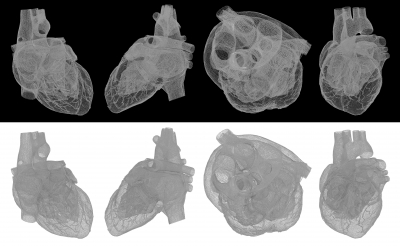

Отличной идеей казалось выполнять шунтирование коронарной артерии (CABG) без остановки деятельности сердца, которое сулило минимизацию грозных осложнений. Но идея не сработала. После роста популярности этого метода в течение предыдущего десятилетия, в 2009 году запустили первое крупное рандомизированное исследование ROOBY, сравнивающее результаты после CABG с полностью остановленным кровообращением и «без насоса» у 2203 пациентов.

Через 30 дней между этими двумя группами не определялось достоверных различий в летальных исходах или осложнениях. Через 1 год комбинированная смертность от какой бы то ни было причины, а также повторная процедура реваскуляризации или нефатальный инфаркт миокарда стали происходить чаще в группе шунтирования с работающим сердцем, чем в группе шунтирования с его остановкой.

Теперь исследователи сообщают о 5-летних результатах ROOBY, которые они опубликовали в New England Journal of Medicine, с дополнительными доказательствами того, что CABG «без искусственного насоса» влечет за собой больше осложнений и более высокую смертность, чем CABG с выключенным кровообращением.

Хоть разница в смертности не оказалась значительной в первый год, она выявилась через 5 лет. Безнасосное шунтирование привело к значительному увеличению риска летального исхода на 28%, а коэффициент смертности оказался 15,2% в группе с сердечной деятельностью и 11,9% в группе «на насосе» (Р = 0,02). Частота основных неблагоприятных сердечно-сосудистых событий составила 31% против 27,1% (Р = 0,046). В итоге не обнаружилось никаких преимуществ, связанных с коронарным шунтированием на работающем сердце.